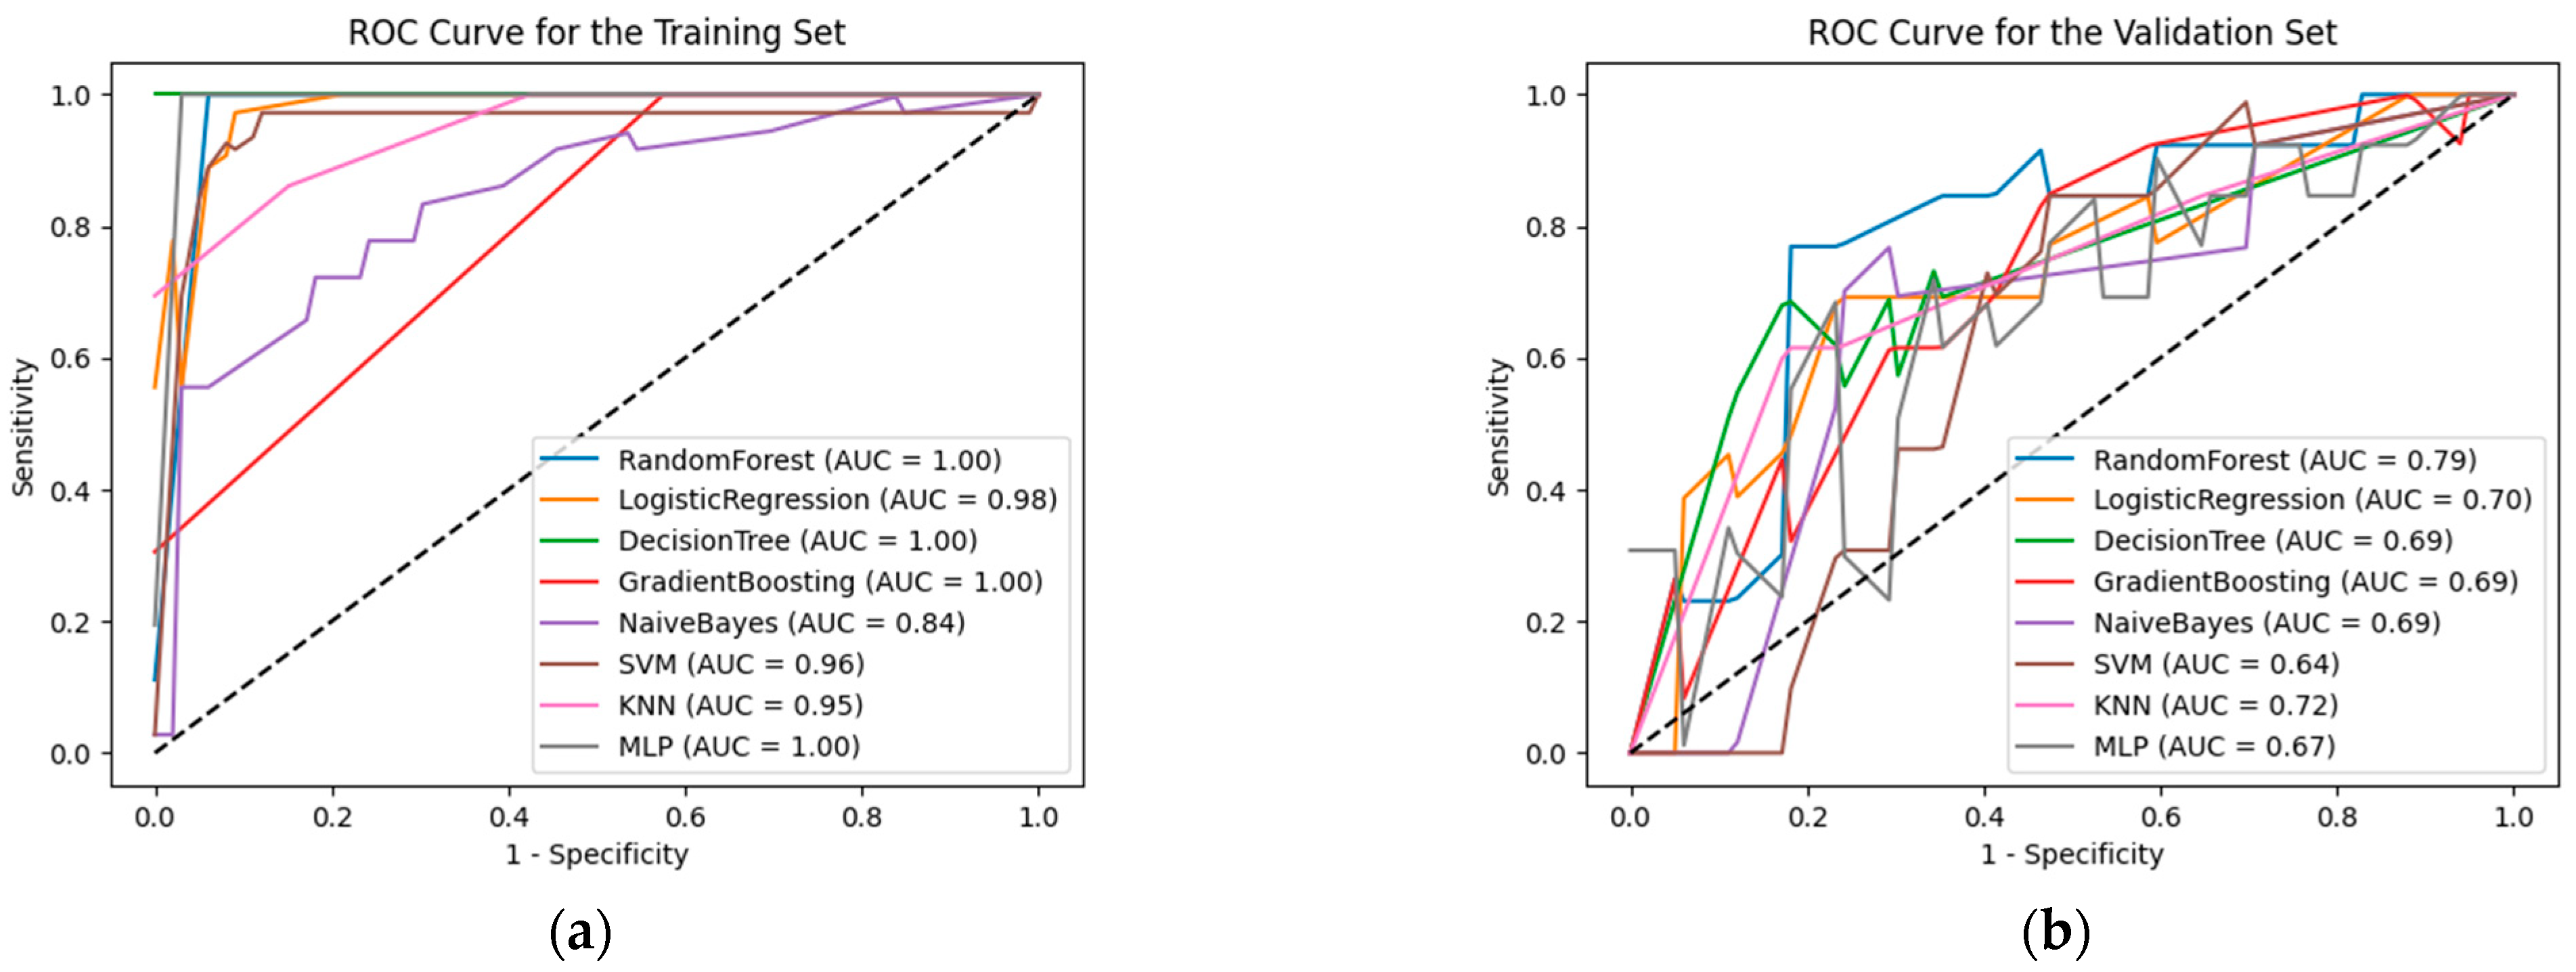

3.3. Model Evaluation